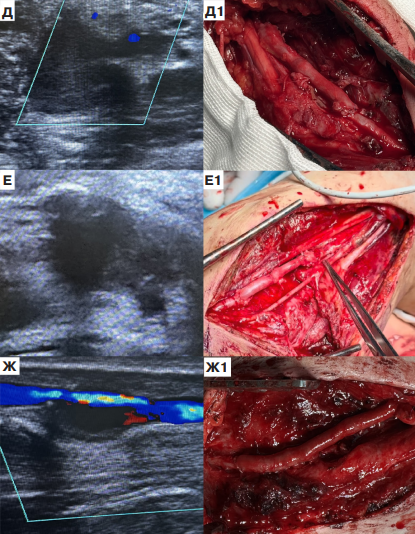

Цель. Провести анализ результатов хирургического лечения пациентов с псевдоаневризмами периферических артерий после осколочного ранения в условиях военно-полевого госпиталя зоны специальной военной операции.

Материал и методы. За период с 01.02.2025 по 01.07.2025 было выполнено 15 реконструктивных операций по поводу посттравматических аневризм периферических артерий. Все пациенты мужчины в возрасте до 44 лет. Сроки диагностики аневризмы всегда превышали 21 сут., что обусловлено отсутствием какой-либо специфичной симптоматики этой патологии. В 73,3% при ранении развивалось кровотечение, которое было остановлено наложением давящей повязки или жгута. Через 19,5±3,5 сут. после ранения, в результате роста аневризмы, прогрессирования периваскулярного отека и воспаления, в 80% случаев проявляются симптомы нейропатии периферических нервов. Результаты. У 80% диаметр псевдоаневризмы достигал 3-5 см. Во всех случаях определялся пристеночный тромбоз ее полости. У 1 пациента выявлено наличие артериовенозной фистулы. Локализацией псевдоаневризмы была: 26,7% подмышечная артерия, 20% плечевая артерия, 13,3% подколенная артерия, 13,3% задняя большеберцовая артерия, 13,3% поверхностная бедренная артерия, 6,7% лучевая артерия, 6,7% глубокая бедренная артерия. У 53,3% выполнено аутовенозное протезирование реверсированной большой подкожной веной, 46,7% резекция участка артерии с анастомозом "конец-в-конец". Во всех случаях осложнений зафиксировано не было. Через 19,5±2,5 сут. после операции нейропатия регрессировала у 7 пациентов из 12. Пациенты с оставшейся неврологической симптоматикой эвакуировались на следующие этапы реабилитации. Остальные вернулись к военной службе.

Заключение. При наличии осколочного ранения конечностей необходимо рутинно проводить ультразвуковое исследование сосудов с целью поиска признаков бессимптомной псевдоаневризмы. Выбор техники операции всегда должен быть персонифицированным, с учетом топографических особенностей поражения. Выраженный рубцовый процесс и близкое расположение периферических нервов создают технические сложности при выделении артерий и удалении аневризмы.